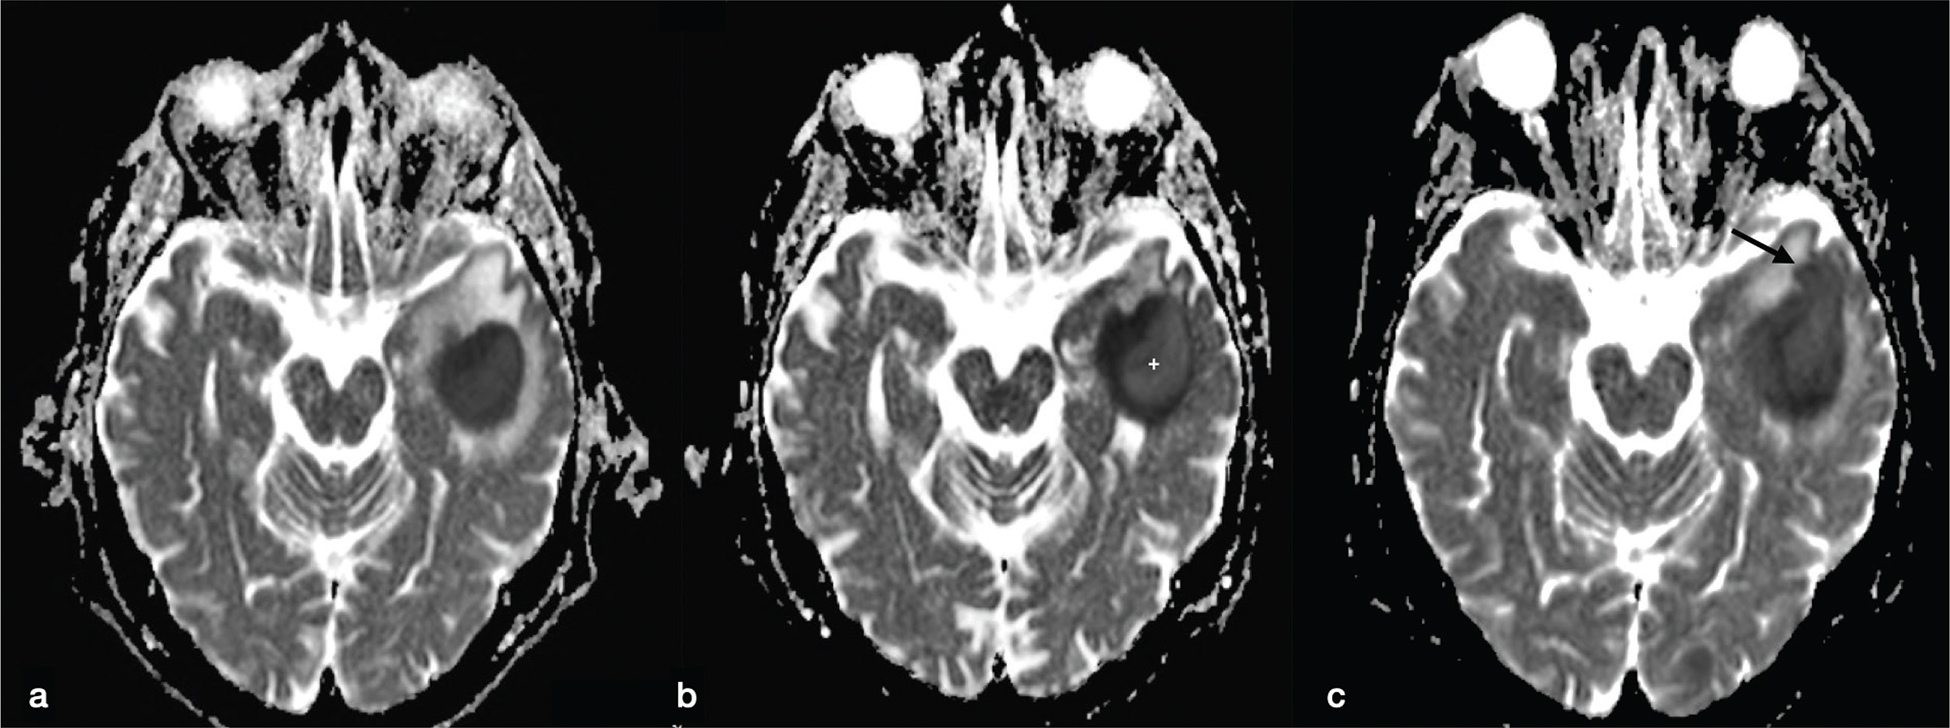

Pyogenic BAs are typically hyperintense on DWI, with low ADC values. This finding is due to the restricted motion of water in the BA cavity that contains pus: inflammatory cells, bacteria, necrotic tissue and a proteinaceous exudate with a very high viscosity and cellularity (Figure 4 and Figures 7-9).11 ADC values may have a wide range due to the different compositions of the abscess cavity, the different types of bacteria involved and the immune response of the host.12,13 Changes in ADC values on post-treatment follow-up MRI may be observed. Increasing ADC values in the abscess cavity are an early indicator of successful treatment (Figure 10). These changes in ADC values can be observed before the size reduction of the BA.12 Conversely, persistently low ADC values could represent an ineffective drug therapy, and recurrence of low ADC values might suggest active disease (Figure 9).14 DWI is also useful in improving the diagnosis of an intraventricular rupture of the BA with subsequent ventriculitis.

FIG 9. Longitudinal Follow-Up MRI Studies of a Pyogenic Abscess in a 54-Year-Old Alcoholic Man Admitted to the ER with Epileptic Seizures. Blood cultures were positive for methicillin-sensitive Staphylococcus aureus. (a) On the first brain MRI, the left temporal lesion showed marked restricted diffusion with low signal intensity on the ADC map, typical for a pyogenic abscess. (b) After 2 weeks of antibiotic therapy (oxacillin: 2 g six times a day) a new MRI was performed. No change in lesion size was observed but increased signal in the central-lateral portion of the core of the abscess on the ADC map was noticed (asterisk) suggestive of good therapy response. (c) Unfortunately, follow-up MRI performed after two more weeks of antibiotic therapy revealed signs of disease progression with an increase in size, satellite lesion (arrow in c), almost unchanged ADC values and more perilesional vasogenic oedema.